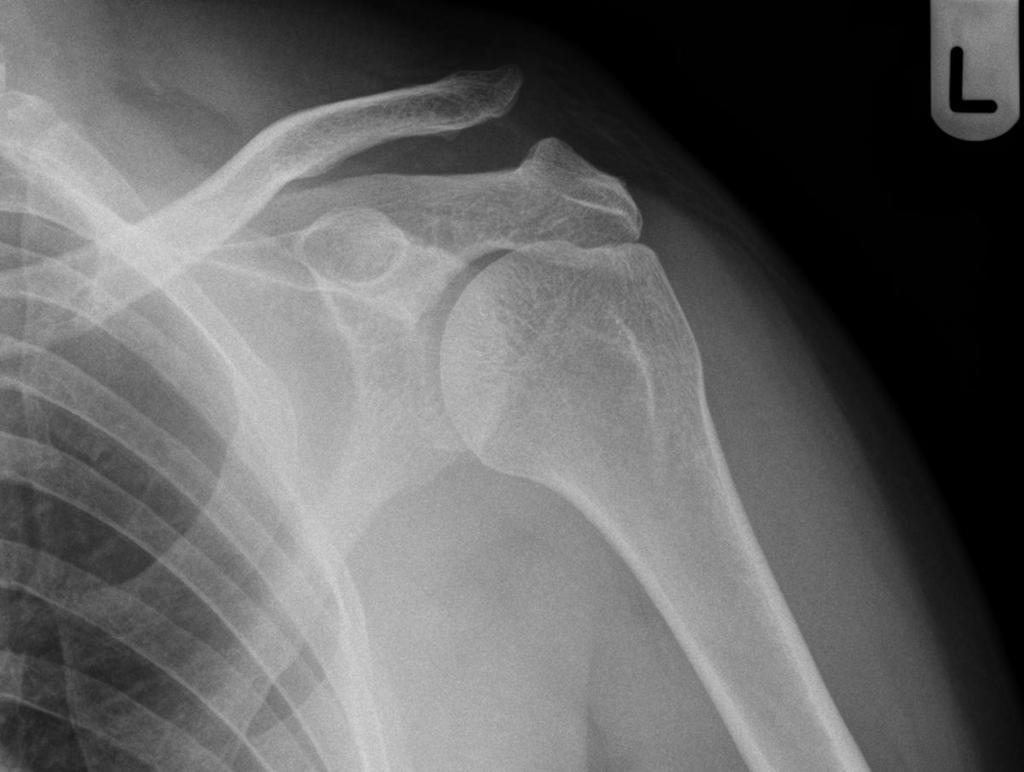

• Acromioclavicular joint separation

• Can obtain stress views (weight bearing) if initial radiographs normal but injury suspected

• Soft tissue swelling or stranding (may be only sign in Type 1)

• Widening of AC joint

• Widening of CC distance

• Superior displacement of distal clavicle (undersurface of clavicle should line up with undersurface of acromion)

• Anterior shoulder dislocation

• Most common shoulder dislocation

• Humeral head is below the coracoid most commonly

• May also be subglenoid, subclavicular, or intrathoracic (very rare)

• May be associated with Hill Sachs lesion

• Compression fracture of posterolateral humeral head, most often in recurrent dislocation (rests against glenoid)

• May be associated with Bankhart lesion of glenoid

• Detachment of anterior inferior labrum from glenoid (bony or soft)